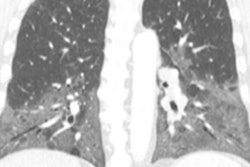

VIENNA - What are the essential aspects to consider when starting a lung cancer screening program using low-dose CT? And why are quality assurance and standardization such important areas? Dr. Mathias Prokop, PhD, from Nijmegen, the Netherlands, provides some answers and also gives some general advice to aspiring researchers.